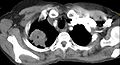

На КТ-скане визуализируется опухоль Панкоста у курящей женщины 47 лет (опухоль обозначена "Р", по гистологическим данным — немелкоклеточная карцинома правого лёгкого).